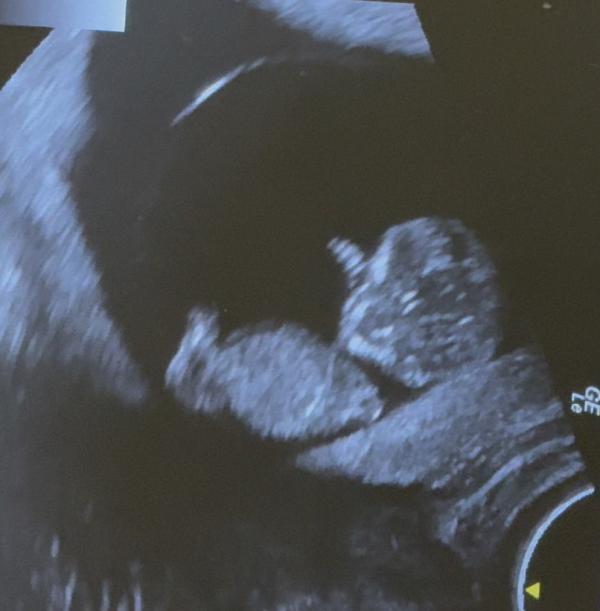

Тревожная мама опять встречалась со своей лялькой 🥰. Но мне так спокойнее 😀

Ниша уже не видна , видимо из за рыхлого эндометрия. В общем ниша не так страшна, как тонкий рубец. Скоро первый скринин, посмотрим, что скажут там.